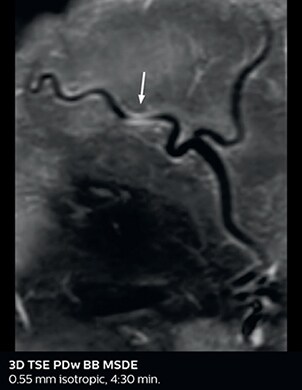

Ultimate precision at maximum speed with Dual AI

Take the leap forward with SmartSpeed Precise, the next generation acceleration technique that expands the proven Compressed SENSE and SmartSpeed technologies with a unique integrated Dual AI innovation, providing ultimate precision at maxiumum speed.

Read more

SmartSpeed Precise